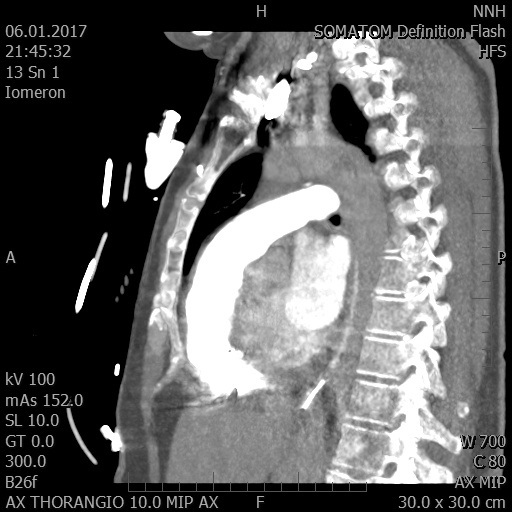

Video 2 - Echokardiograficky byla zjištěna těžká dysfunkce dilatační levé komory s nezvětšenou pravou komorou.Pro nejasnou příčinu zástavy jsme provedli i vyšetření výpočetní tomografií (CT), které vyloučilo plicní embolizaci (série 1 - soubory na konci článku). V den přijetí při přetrvávající oběhové nestabilitě byla nemocná opakovaně defibrilována pro fibrilaci komor se stabilizací rytmu po podání amiodaronu a mesocainu. Dle hemodynamických měření se jednalo o těžký kombinovaný šok. Vstupní laboratorní vyšetření bylo bez větších pozoruhodností. Posléze jsme doplnili anamnézu od příbuzných a zjistili, že pacientka užila do dvou hodin před srdeční zástavou první tabletu amoxicilinu na lehký respirační infekt. Při nevýtěžnosti vstupních vyšetření a nových anamnestických informacích jsme doplnili 14 hodin po kolapsu vyšetření koncentrace tryptázy v séru, která byla extrémně zvýšena (tabulka 2), což nás vedlo k podezření na anafylaxi.